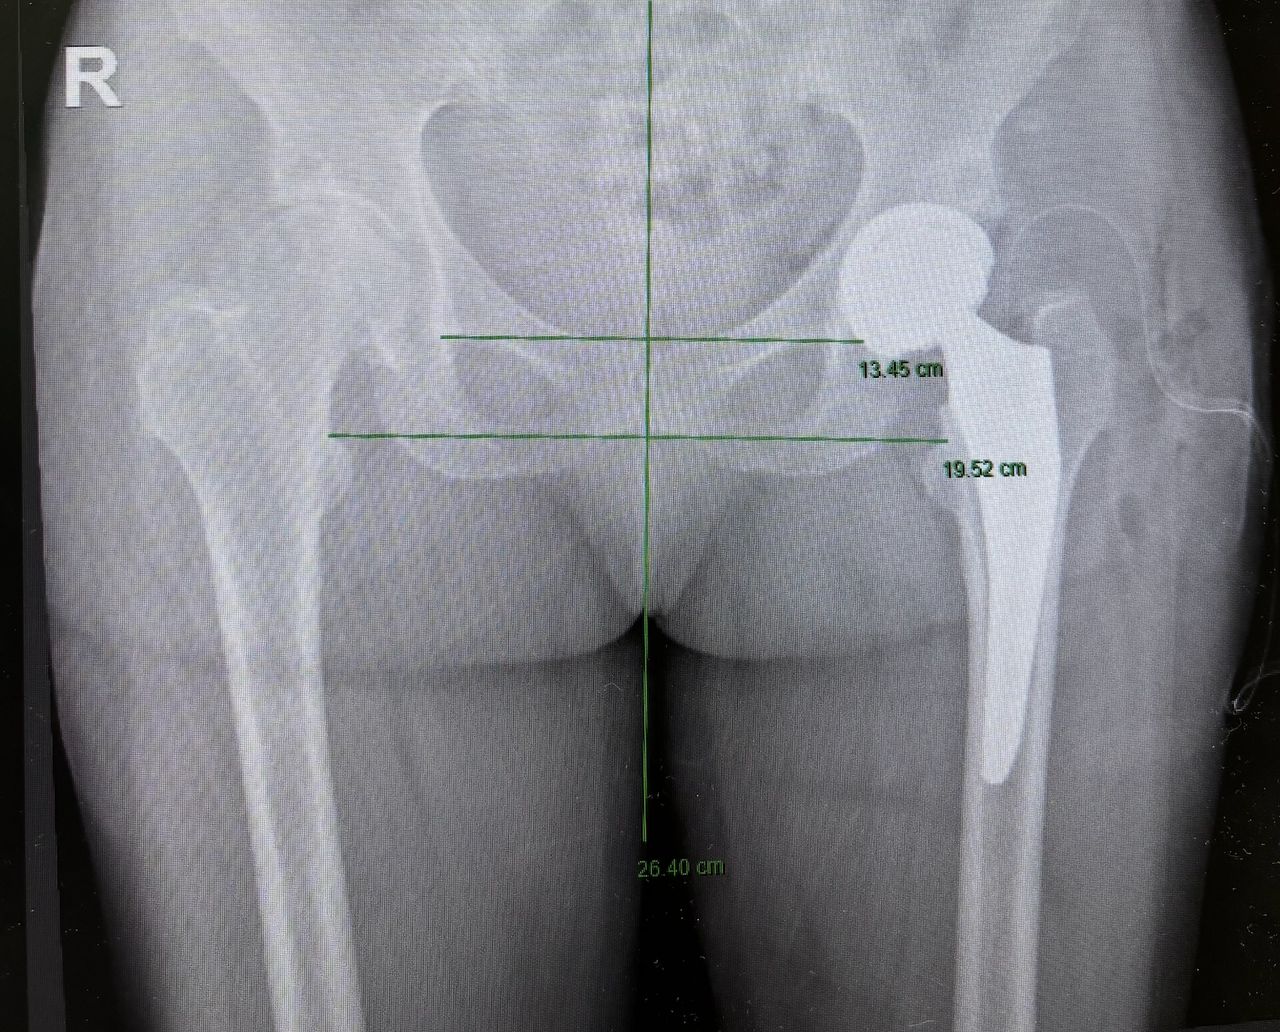

Ho maturato una solida esperienza nella chirurgia protesica mini-invasiva di anca e ginocchio. Eseguo interventi di protesi di anca mediante accesso anteriore “bikini” e accesso posterolaterale, interventi di protesi di ginocchio sia monocompartimentale che totale. Tratto la traumatologia sportiva di ginocchio e spalla mediante l’utilizzo di tecniche artroscopiche mini-invasive.